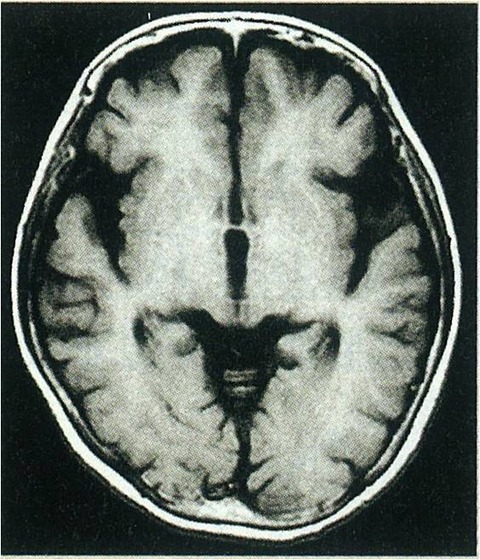

クローン病なんだが質問ある?